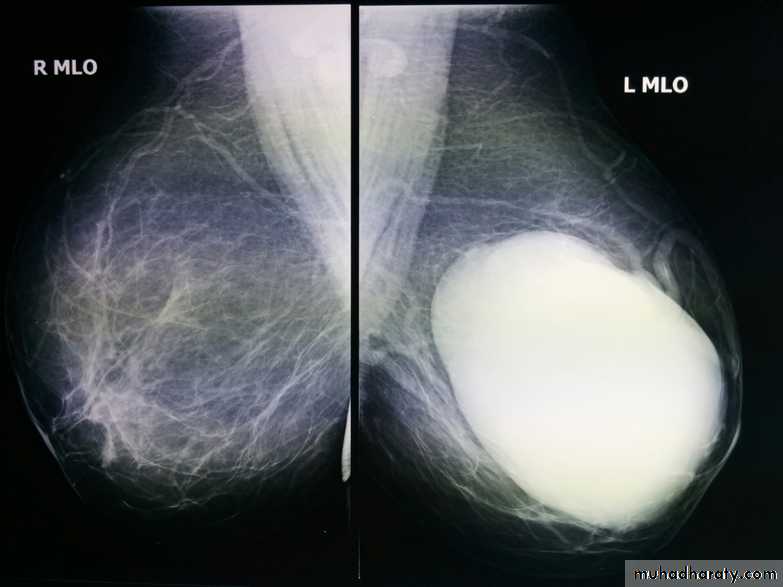

The mediolateral oblique (MLO) view is one of standard mammographic views. It is the most important projection as it allows to depict most breast tissue.

The sensitivity of mammography for the detection of ILC reportedly ranges between 55-80% 8. Because of the limitations of mammography in detecting ILC, other modalities, such as sonography and MR imaging, are being used in evaluating clinically suspicious findings and known cancers to assess the extent of disease. ILC are more commonly seen on the craniocaudal (CC), compared to the mediolateral oblique (MLO).